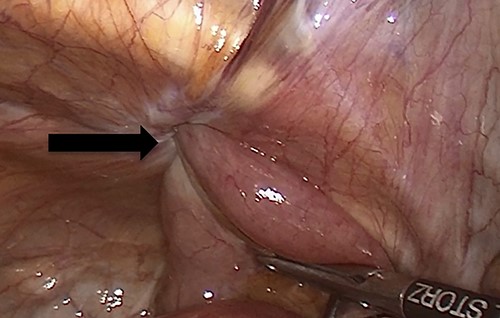

Due to the high-grade small bowel obstruction, the patient was pushed as an emergency case to the operating room. The surgery started and ended as a laparoscopic procedure with three small incisions; 12, 11 and 5 mm port sizes located supraumbilically, right and left midclavicular line relatively. Once the peritoneum was penetrated, and gas insufflated, diagnostic laparoscopy was done, and the obturator hernia with bowel content was visualized (Fig. 3), with a transitional zone at the hernia site showing a proximal dilatation and distal collapse of the small bowel. After that, reduction of the hernia content was subsequently made with no signs of gangrene or ischemia of the bowel. Then, the small bowel was run as a whole to eliminate any other transitional zones or pathology, which was unremarkable. Therefore, as there was no contamination, ischemia or perforation, a Vicryl mesh was elected and inserted as a plug into the obturator opening using a peritoneal flap and fixed (Fig. 4). Once the fixation was obtained, a ProGrip mesh was then applied to cover the whole right area (Fig. 5), which was covered by the peritoneum afterwards. The abdomen was inspected and the bowel looked healthy. Lastly, the ports were removed, the incisions were closed, the skin was clipped and then the dressing was applied.

An intraoperative figure of the Vicryl mesh plug inserted into the obturator opening.